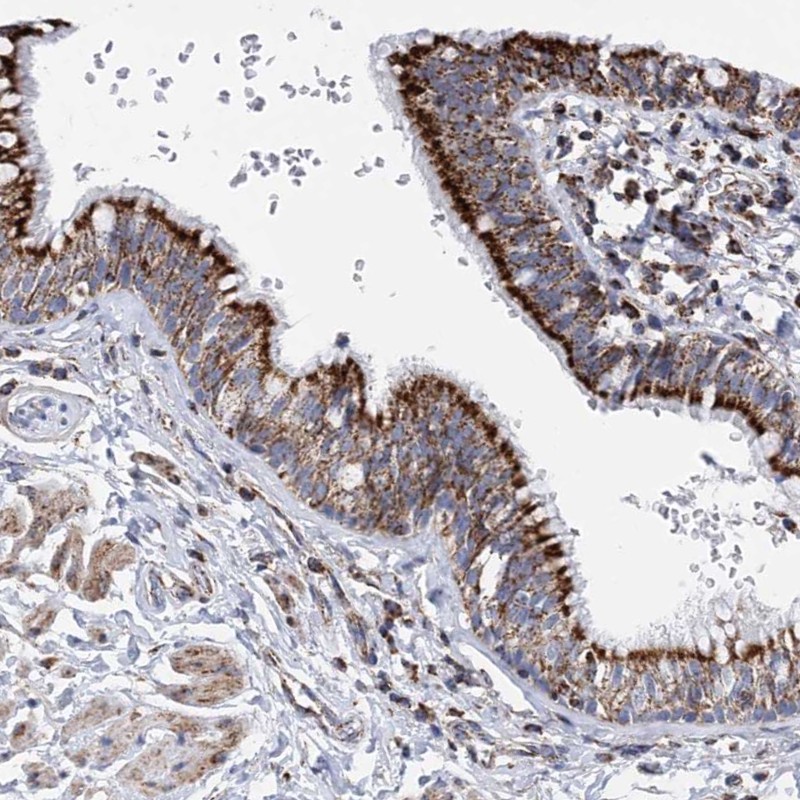

Immunohistochemical staining of human bronchus shows strong granular cytoplasmic positivity in respiratory epithelial cells.